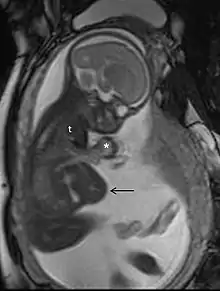

تصوير بالرنين المغناطيسي

التصوير بالرنين المغناطيسي، بدون وسط تباين في التصوير بالرنين المغناطيسي، لا يرتبط بأي خطر على الأم أو الجنين، وإلى جانب تخطيط الصدى الطبي هو الأسلوب المفضل للتصوير الطبي في الحمل.[1]

استخدامات شائعة

يستخدم التصوير بالرنين المغناطيسي عادة في النساء الحوامل المصابات بالألم البطني و / أو الألم الحوضي، أو في الاضطرابات العصبية المشتبه فيها، وأمراض المشيمة، والأورام، والعدوى، و / أو الأمراض القلبية الوعائية.[3] تعطي معايير الاستخدام المناسبة من قبل الكلية الأمريكية للأشعة تصنيف ≥7